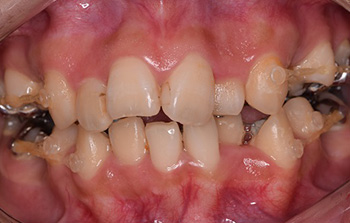

歯やあごの状態を正確に知るために、口や顔の写真、レントゲン写真(頭部X線規格写真、パノラマ等)、歯型などの資料を採ります。特に頭部X線規格写真(セファログラム)は、上下のあごの大きさやそのバランス、あごや唇の形態、歯の傾斜角度、口元のバランスなどの状態を正確に知ることができる検査です。